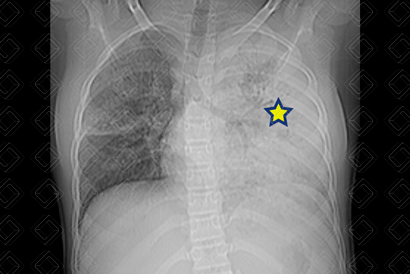

Texto alternativo para a imagem Figura 1. Créditos: Dra. Elazir Mota - Rio de Janeiro/RJ

Descrição da figura 1: Caso 1: Radiografia de tórax PA. Hemitórax opaco esquerdo com volume torácico mantido (asterisco) - semelhante dos dois lados. Observe a traqueia centralizada.